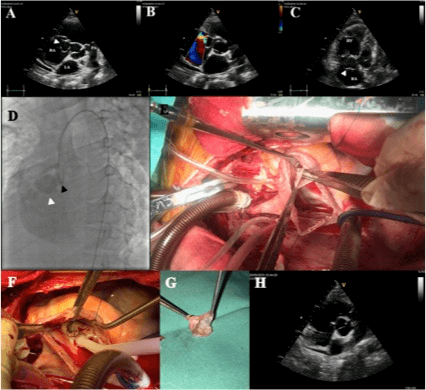

A transthoracic echocardiogram revealed mildly decreased left ventricular ejection fraction, competent auriculoventricular valves, moderate size circumferential pericardial effusion without signs of cardiac tamponade. A big mobile aneurysmal sac protruding into the right atrium (RA) was detected and a ruptured aneurysm of the right coronary sinus of Valsalva was suspected. Echocardiographic colour flow Doppler confirmed continuous flow between the aneurysmal sinus and right atrium (Figures 1A-1C). A cardiac catheterization revealed a competent aortic valve and the aneurysm originating from the right coronary cusp of the valve protruding and draining into the RA adjacent to the tricuspid valve (Figure 1D).

Surgical repair was performed subsequently. After sternotomy 1500ml of serous fluid were drained from the right pleura and pericardium cavity. The RA was severely dilated, and a thrill palpated. After cardiopulmonary bypass and aortic cross clamp, transverse aortotomy was carried-out at the root to deliver antegrade cardioplegia through both coronary ostium. Through right atriotomy (Figure 1E), a “windsock” aneurysm of the right coronary sinus (20 mm x 15 mm) was observed protruding into the RA, immediately above the tricuspid valve plane, with two 5 mm perforations at the end. After aneurysm resection, the 5 mm fistulous tract was closed with a double running autologous pericardium pledgeted 4-0 prolene suture (Figures 1F-1G). After aortic and atrium closure was achieved, the cross clamp was removed, the patient recovered sinus rhythm and was weaned off from cardiopulmonary bypass uneventfully.

Figure 1: A) Transthoracic echocardiogram. Parasternal short axis view: aneurysmatic sac (white arrow) in the right atrium below the tricuspid valve. B) Parasternal short axis view: color Doppler flow from the aneurysm sac to the right atrium. C) Four apical chambers view with focus on the right ventricle: dilated right ventricle and aneurysm sac (white arrow) below the tricuspid valve. D) Aortogram: deformation of the right coronary cusp (black arrow) with the aneurysmatic sac (white arrow) filled by contrast revealing flow into the right ventricle. Also a closed aortic valve is seen with no incompetence. E) Intraoperative photograph of ruptured aneurysm of the right sinus of Valsalva with a "windsock" morphology, seen through a right atriotomy (forceps inside the sac). F) Surgical view after surgical closure of fistulous tract with doble layer prolene suture. G) Ruptured aneurysm sac resected. H) Follow-up transthoracic echocardiogram picture with the sinus of Valsalva repaired.

Follow up transthoracic echocardiogram revealed no residual leak and trivial aortic regurgitation. All three aortic sinuses have normal appearance. The patient was discharged at day 5 postoperatory in good conditions. Sinus of Valsalva aneurysm (SVA) is a rare disease that has an incidence of 0.14%-0.23% in Western series. The right coronary cusp is most affected (65%-86%) and most commonly rupture into the right ventricle (75%) [2, 3]. Most cases remain asymptomatic but symptoms such as acute dyspnea, chest pain and heart failure may arise if the aneurysm ruptures [4]. Cardiovascular anomalies are found in 40-50% of children with Down syndrome, the most common being septal defects and tetralogy of Fallot. Few cases have been reported of SVA rupture in patients with Down’s syndrome [1, 4-6].